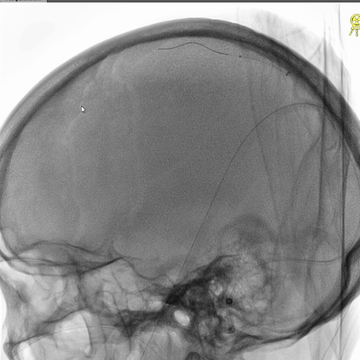

直窦再次微导管造影:直窦血液引流可。

6*30mm球囊扩张右侧横窦-乙状窦和颅底位置颈内静脉,辅以球囊滑动技术。

介入治疗后右侧颈动脉造影:上矢状窦、直窦和右侧横窦-乙状窦均见显影,右侧横窦局部狭窄明显。